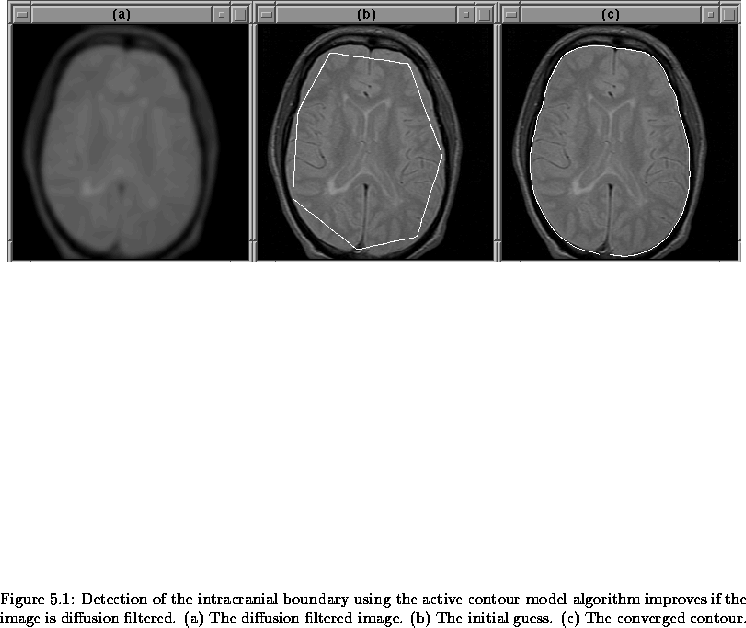

Figure 5.6 shows the results of the active contour algorithm on slice 16 of Data Set 1 (see Section 8.2). The algorithm converged in about 5 iterations and has reasonably located the intracranial boundary. The initial guess in this case was very good.

Figure 5.6: An active contour can detect the intracranial boundary. (a) The initial guess. (b) The converged contour.

5.3.2 Contribution of Diffusion Filtering

The active contour algorithm improves when the image contains little noise and soft, but obvious, edges. The improvement comes from the fact that, in such an image, the contour is unlikely to attach itself to noise and is more likely to find the wider edges.

Figure 5.8 is an igraph similar to that shown in the previous section. In this case, however, the input image is diffusion filtered (see Chapter 4) to soften edges and reduce noise. Figure 5.9 shows the results from this igraph. The initial contour is the same as that in Figure 5.7. This time, however, the intracranial boundary is detected.